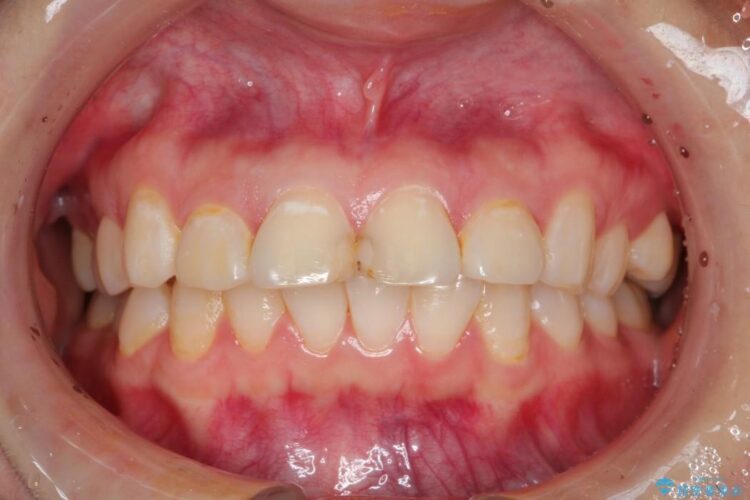

【20代女性】出っ歯の矯正 治療例

口元が出ていることを気にされて来院されました。

出ている歯を引っ込めるためのスペースを作るため、上下左右の小臼歯を抜歯し、ワイヤー矯正を行いました。治療後は、口元がスッキリとしたことで患者様にも喜んでいいただきました。